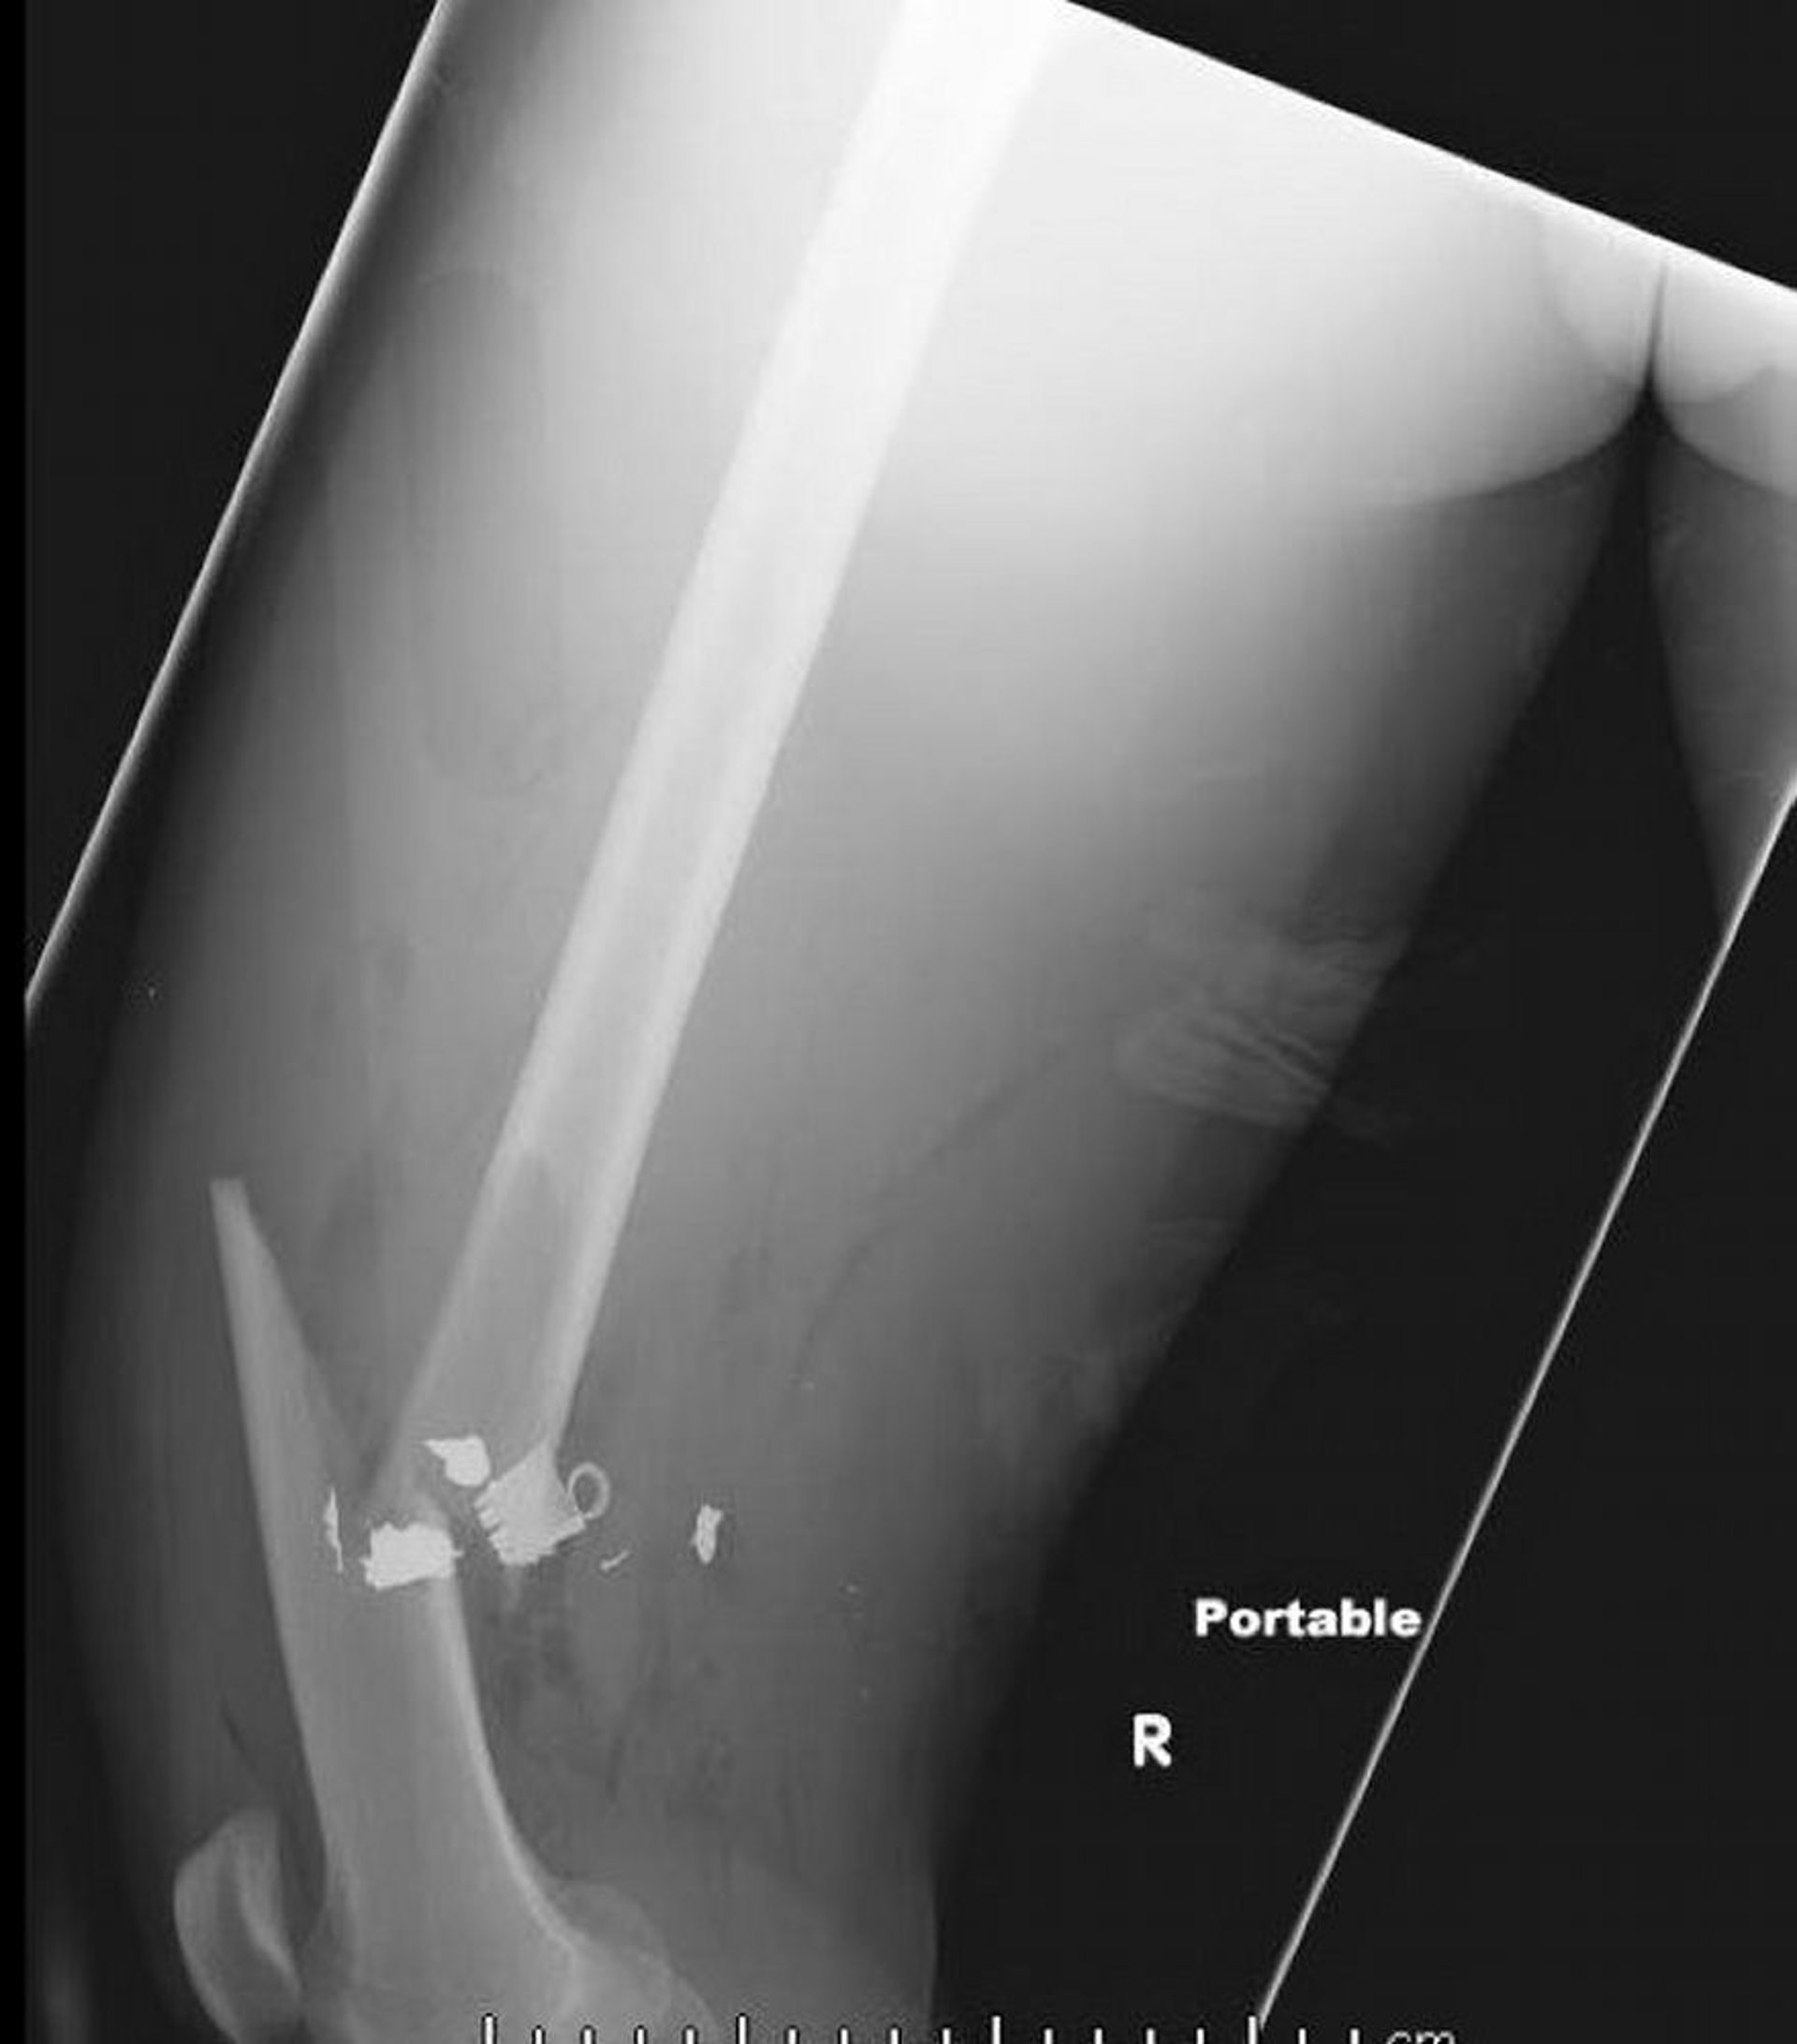

Перелом средней трети бедренной кости (2)

На данном рентгеновском снимке бедренной кости в боковой проекции изображен перелом средней трети бедренной кости с участками воздуха и зафиксированными инородными телами металлической плотности в мягких тканях.

Image courtesy of Danielle Campagne, MD.